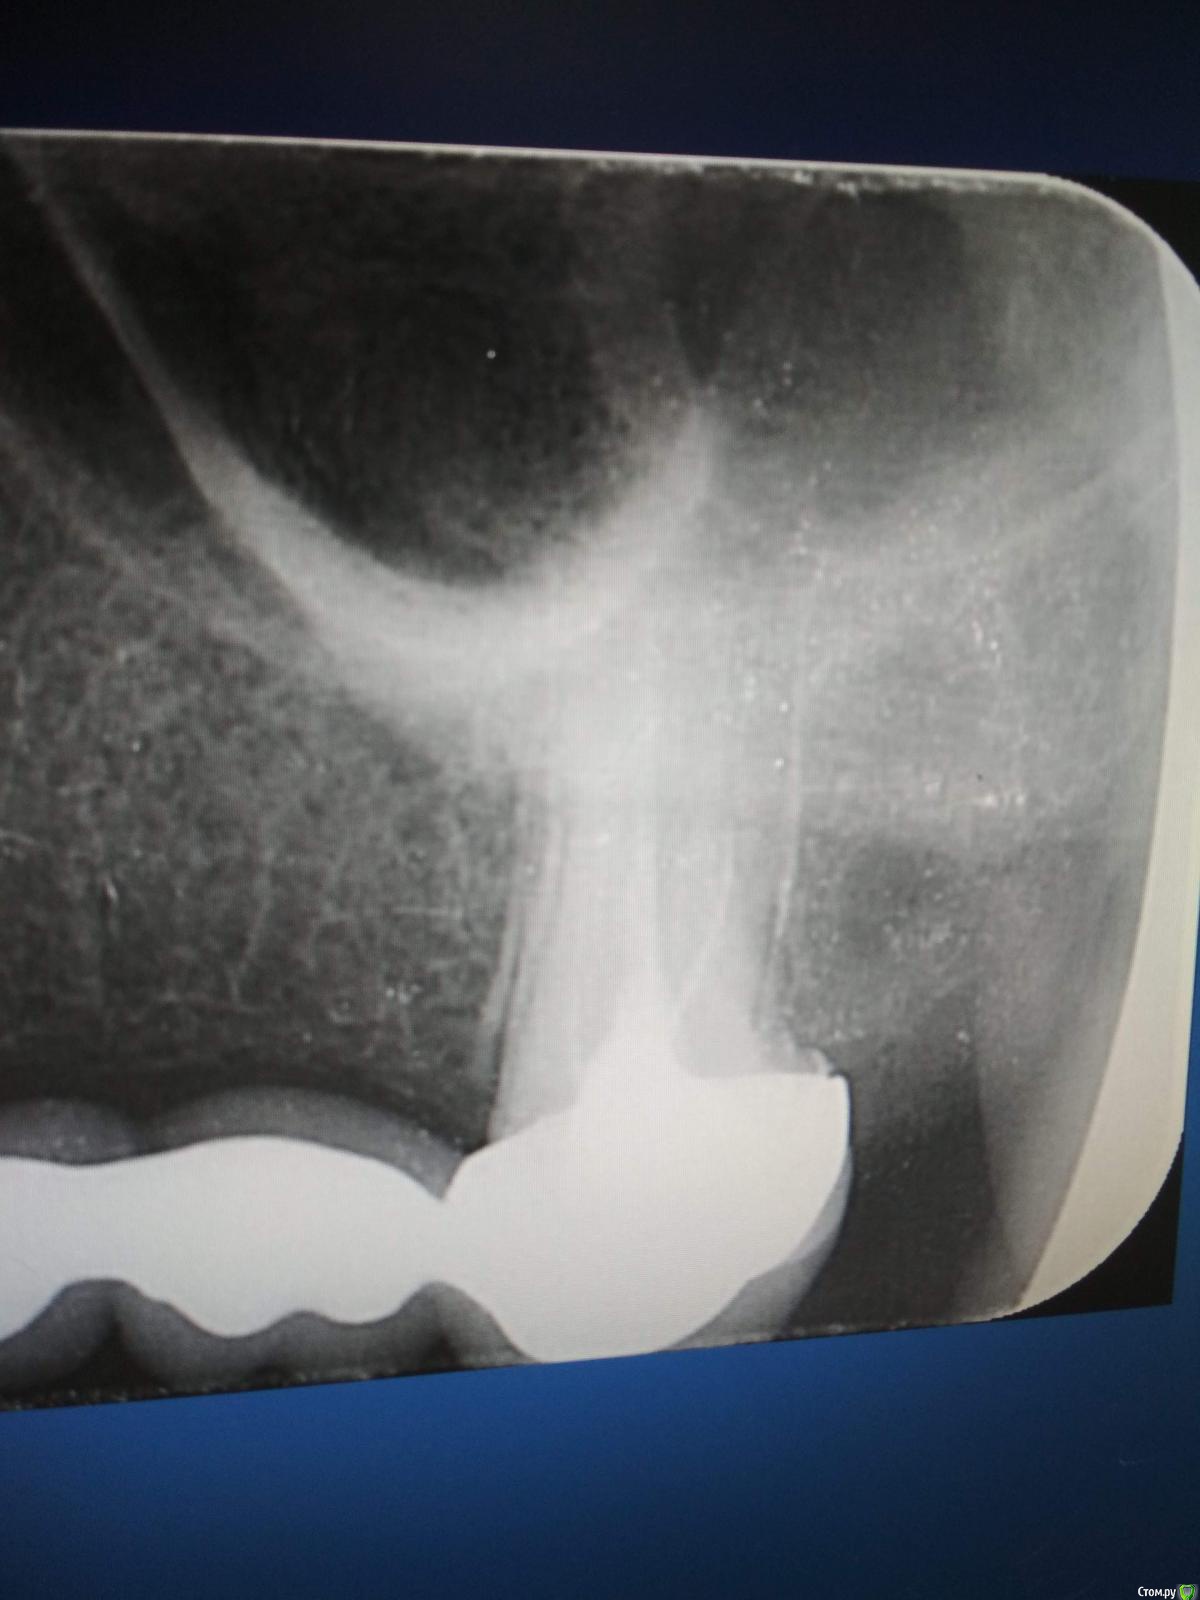

Arsinoya Опубликовано 5 октября, 2019 Автор Поделиться Опубликовано 5 октября, 2019 Здравствуйте, есть еще вот такой снимок, это как раз когда все боли начались, еще до перепломбировки каналов Ссылка на комментарий

Мартовский Опубликовано 7 октября, 2019 Поделиться Опубликовано 7 октября, 2019 Шестых зубов у вас нет, ни с лева ни с права, ни с верху ни с низу. Перфорация есть в левой четверке. Что делать, вам уже сказали: обратиться к другому врачу, по интернету такое не вылечить. Ссылка на комментарий